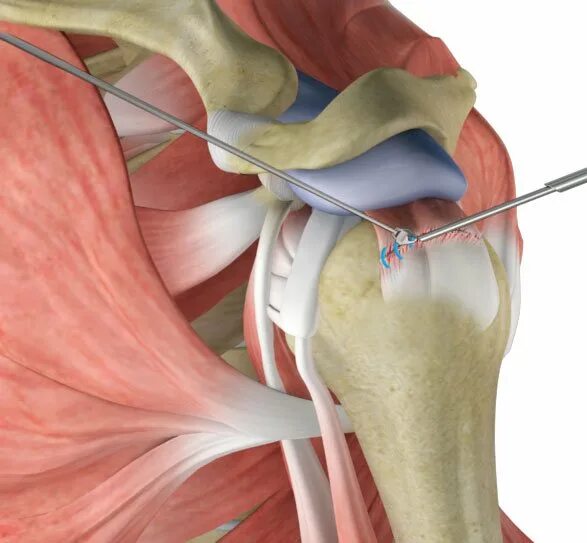

Разрыв длинных сухожилий